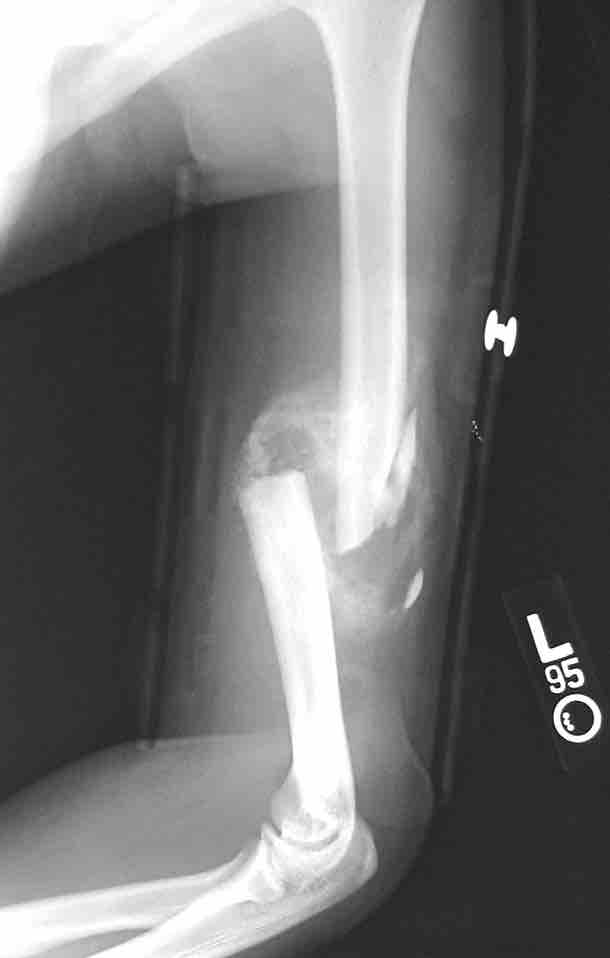

Healing fracture

This figure depicts a radiograph of a child's healing supracondylar humeral fracture that has been treated with closed reduction and pinning. This image, taken three weeks post injury, demonstrates the benign periosteal reaction of normal healing bone.

This is a radiographic image (x-ray) of a child's healing supracondylar humeral fracture that has been treated with closed reduction and pinning. This image, taken three weeks post injury, demonstrates the benign periosteal reaction of normal healing bone.